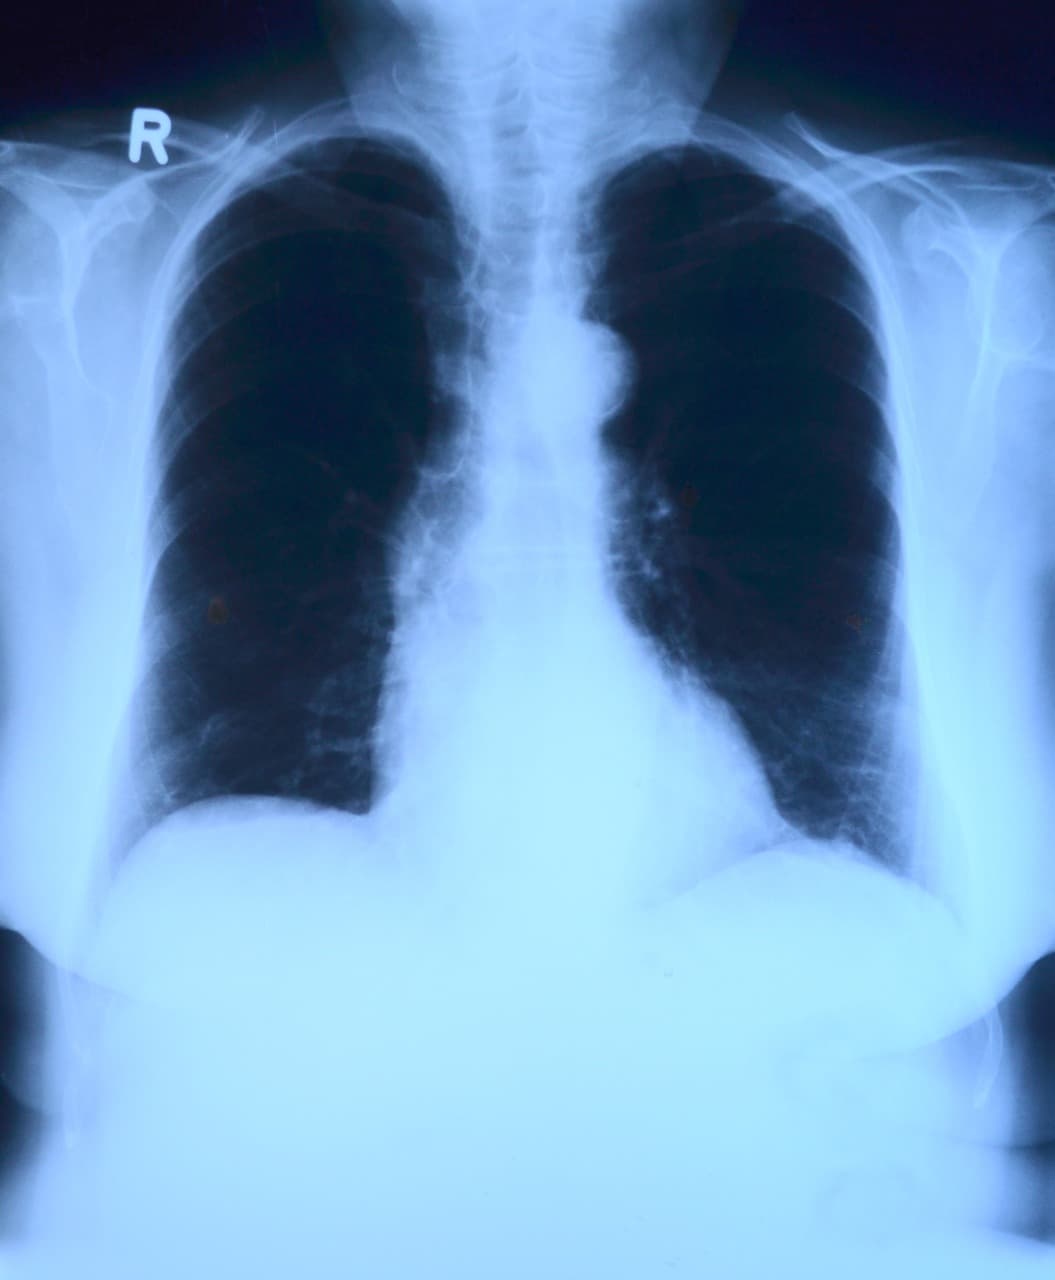

폐렴 진단을 위한 검사

- 흉부 X-ray : 폐 음영 확인

- 혈액검사 : 백혈구 증가, CRP 수치 확인

- 객담 검사 : 병원체 확인

- 산소포화도 측정 : 저산소증 확인